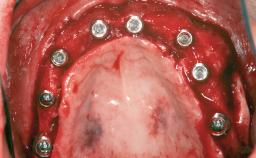

# of Teeth 6

# of Implants 4

Type of Implants One-Piece|Reduced-Diameter

Bone Augmentation Horizontal|Simultaneous|Sinus Floor Elevation|Staged